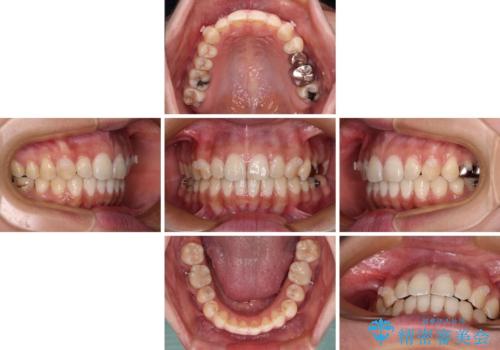

- 下顎の前歯が隠れていることと、デコボコを気にして来院された患者様です。

目立ちにくい装置を希望されていたため、ワイヤー装置とインビザラインを提案したところ、インビザラインを希望されました。

銀歯やムシ歯処置の必要な歯が奥歯にあり気になっていたので、矯正治療の途中でセラミッククラウンへ変更し、その後歯列を仕上げていくこととしました。

咬み合わせと目立っていた銀歯が改善され、患者様には大変満足していただきました。